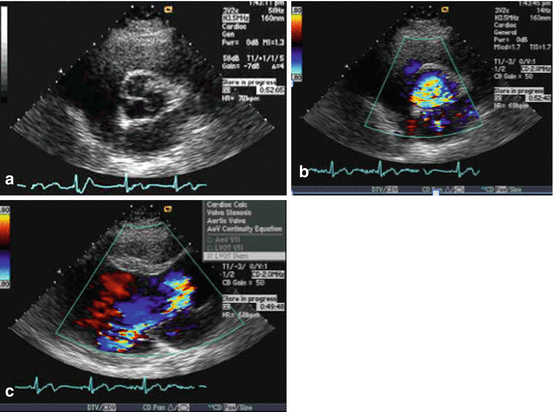

Austin Flint Murmur